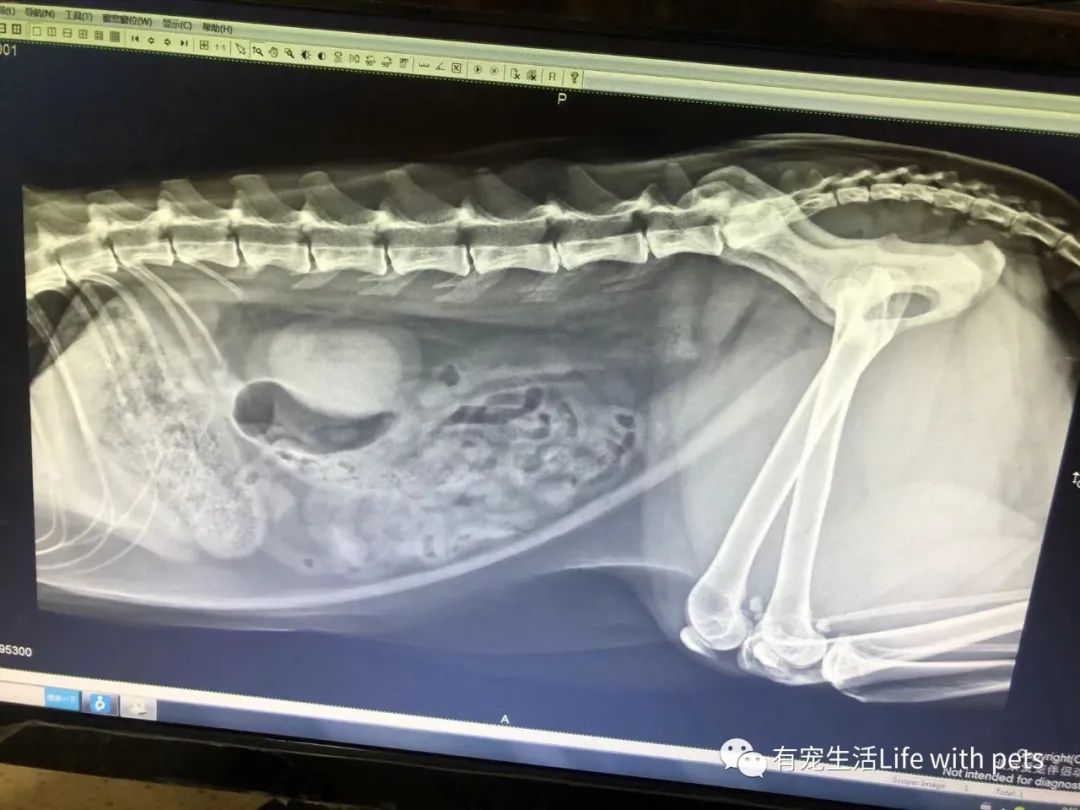

经检查,医生说:膀胱只有一颗很小很小的结石(结晶),另一颗变小后顺着尿道排下来,但卡到尿道口了(医生指着B超给我看,但结石的亮点太小,实在没拍出来),因此引起尿频、出血。